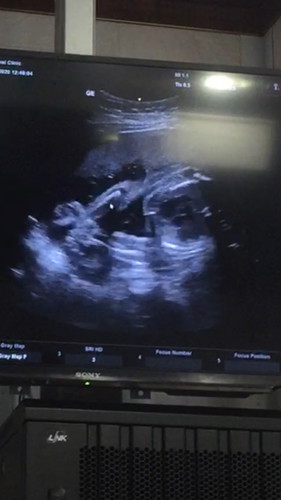

ลูก

มีใครพอจะดูออกไหมค่ะ ผญ. หรือ ผช. 7เดือนดูไม่รู้สักทีเลย ?

ชายค่ะ

กำลังตั้งครรภ์